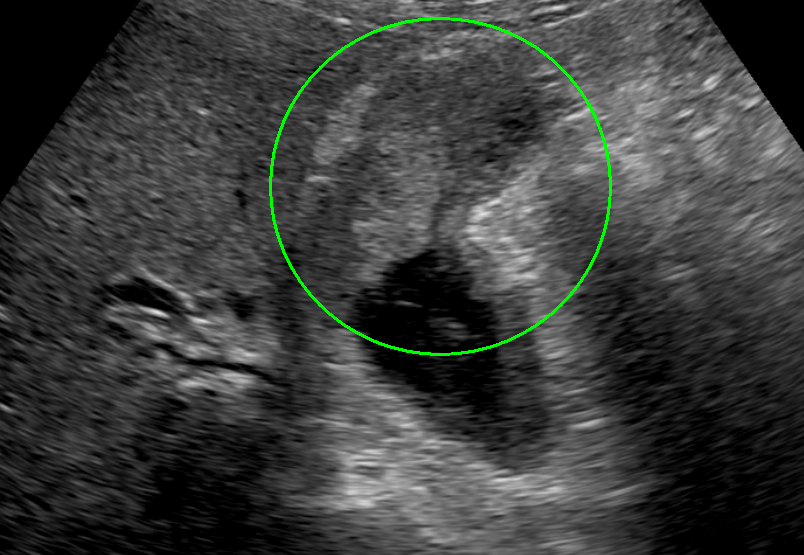

検査画像

超音波内視鏡(EUS)画像